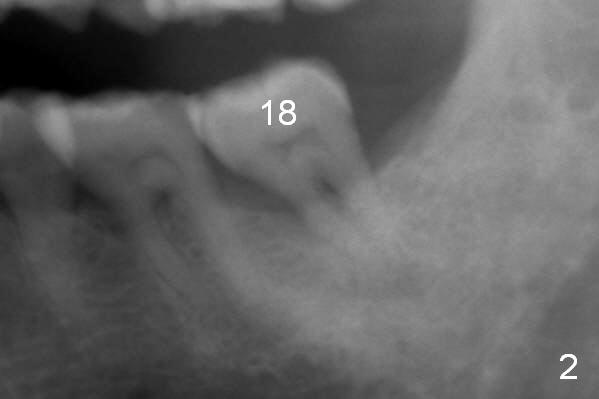

A 59-year-old man has history of chronic periodontitis (Fig.1 (taken in 2005), 2 (2014), 3 (2016)) involving the tooth #18. The bone loss may be complicated by bruxism. Large crown vs. narrow roots contributes to severe bone loss. An implant should be as long as possible and placed as coronally as possible to tackle crown/implant ratio issue. To prevent peri-implantitis, the implant may have to be placed deep. It appears that the bone height is more favorable mesially than distally (Fig.3). After extraction of the supraerupted and loose tooth (Fig.4; no Antibiotic), explore the socket to determine the favorite osteotomy site, most likely the mesial socket, lingually.